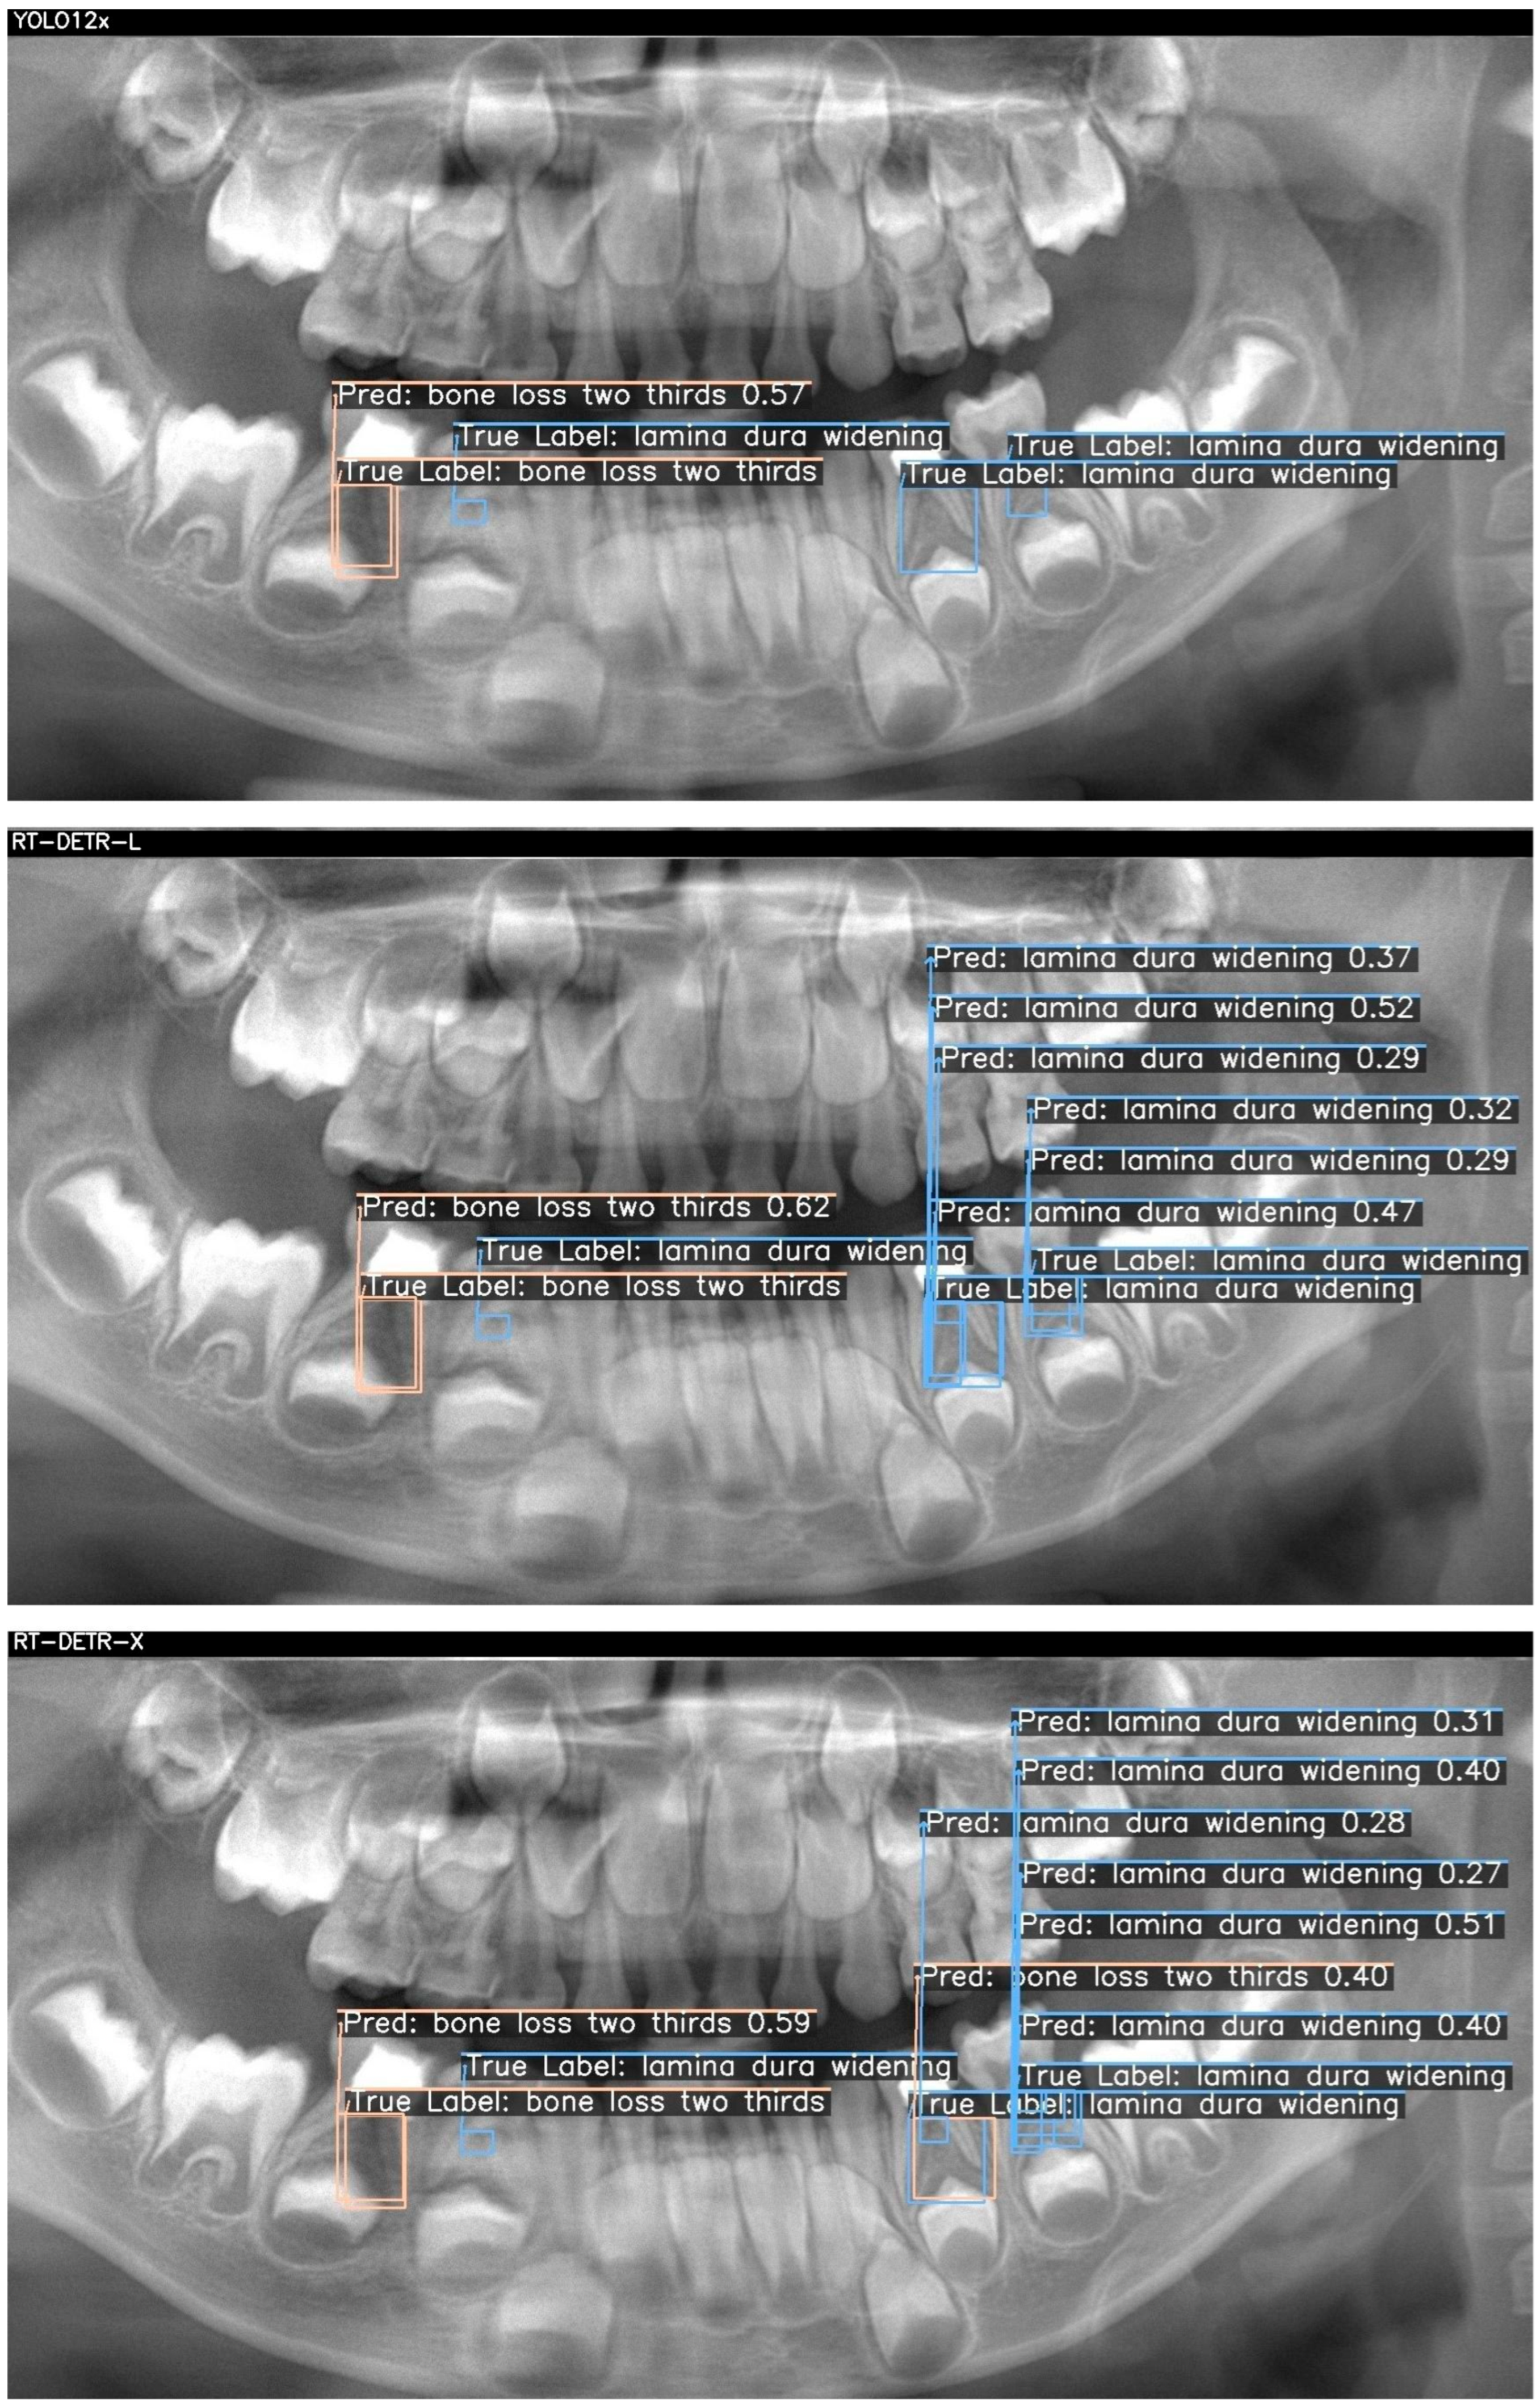

Below, two sample cases are presented as Figure 2 and Figure 3. For each case, outputs from YOLOv12x (top), RT-DETR-L (middle), and RT-DETR-X (bottom) were displayed. The "True Labels" annotated by the expert and the prediction (Pred) boxes marked by the model were color-coded in green, blue, and orange to differentiate the diseased regions during visualization.. Figure 2 and Figure 3 visualize these differences, showing that YOLOv12x frequently misses subtle lamina dura changes, RT-DETR-L captures more lesions but at the expense of false positives, while RT-DETR-X maintains superior balance by detecting both conspicuous and subtle lesions with minimal error. These visualizations further confirm the trends seen in Table 7.

Figure 3 presents two true lesions: a “bone loss two thirds” in the lower left molar region and a “lamina dura widening” immediately adjacent. YOLO12x again excels at the conspicuous lesion, correctly identifying the bone loss (0.57) but missing the subtle widening (TP = 1, FN = 1, FP = 0). RT-DETR-L captures the bone loss (0.62) but overpredicts widening, generating multiple false positives (TP = 1, FN = 1, FP = 3), indicating class–label confusion despite high recall. As shown in Table 7, RT-DETR-X delivers the most reliable performance here as well, detecting both lesions (bone loss: 0.59; widening: 0.27–0.40) with only one false positive (TP = 2, FN = 0, FP = 1) and consistent confidence levels, underscoring its suitability for exhaustive lesion screening. Table 7 presents the case-level detection metrics corresponding to Figure 2 and Figure 3, confirming the numerical distribution of TP, FN, and FP values observed in the visual outputs.